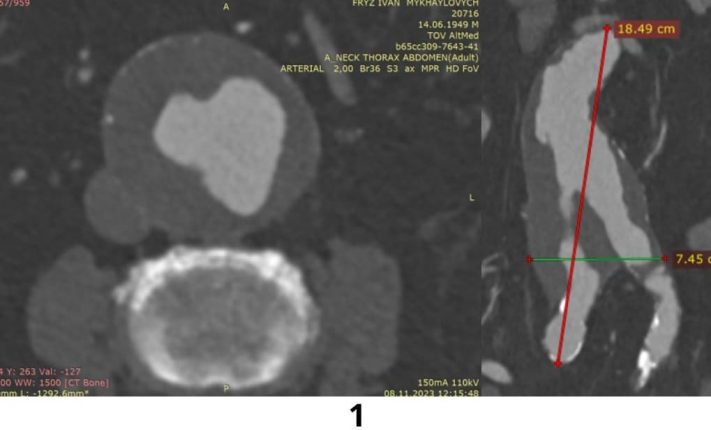

Чоловік поступив у ЦМКЛ з хронічною аневризмою черевного відділу аорти з поширенням на загальні клубові артерії. Розміри аневризми складали 18,5 х 7,5 х 6,4 см. Від аневризми відходила одна з ниркових артерій та нижня брижова артерія, яка кровопостачає кишечник. Отже, крім високої загрози розриву, який в абсолютній більшості випадків є смертельним, аневризма також загрожувала життєдіяльності нирок та кишечника.